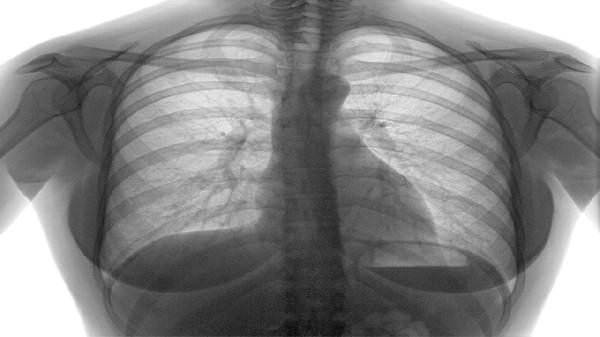

呼吸肌无力引发潮式呼吸或下颌式呼吸,表现为深浅不一的喘息或长时间呼吸暂停。血氧饱和度下降可能使口唇发绀,床头抬高30度可缓解呼吸困难。医护人员可能采用低流量吸氧或支气管扩张剂改善通气。